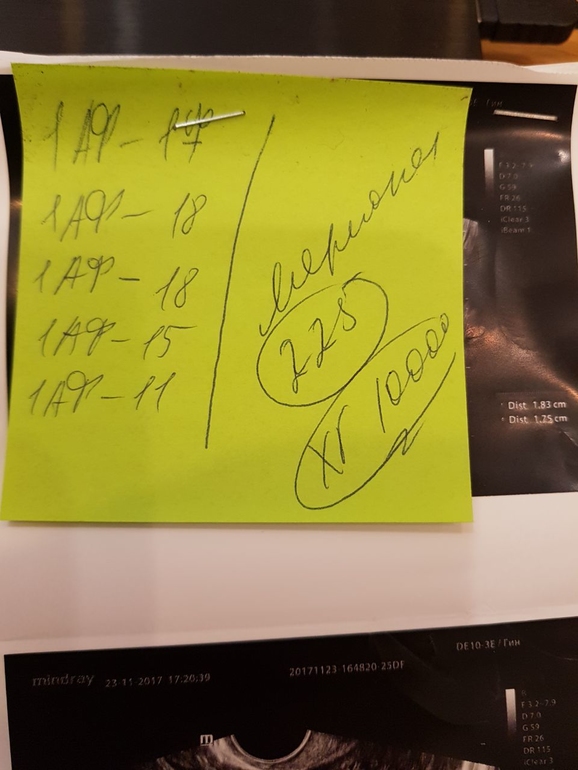

На этом мерионале, потом мне дозировку подняли, правда, выросло еще несколько фоликулов: на второй пункции мы получили все, из них 3 зрелых клетки, причем, я так понимаю, из тех, которые были ровные по 17-18 мм.

Это картинки с последнего узи перед пункцией вроде, не помню. Мне кажется да, потому что там написан ХГ, наверно за сутки ДО пункции.